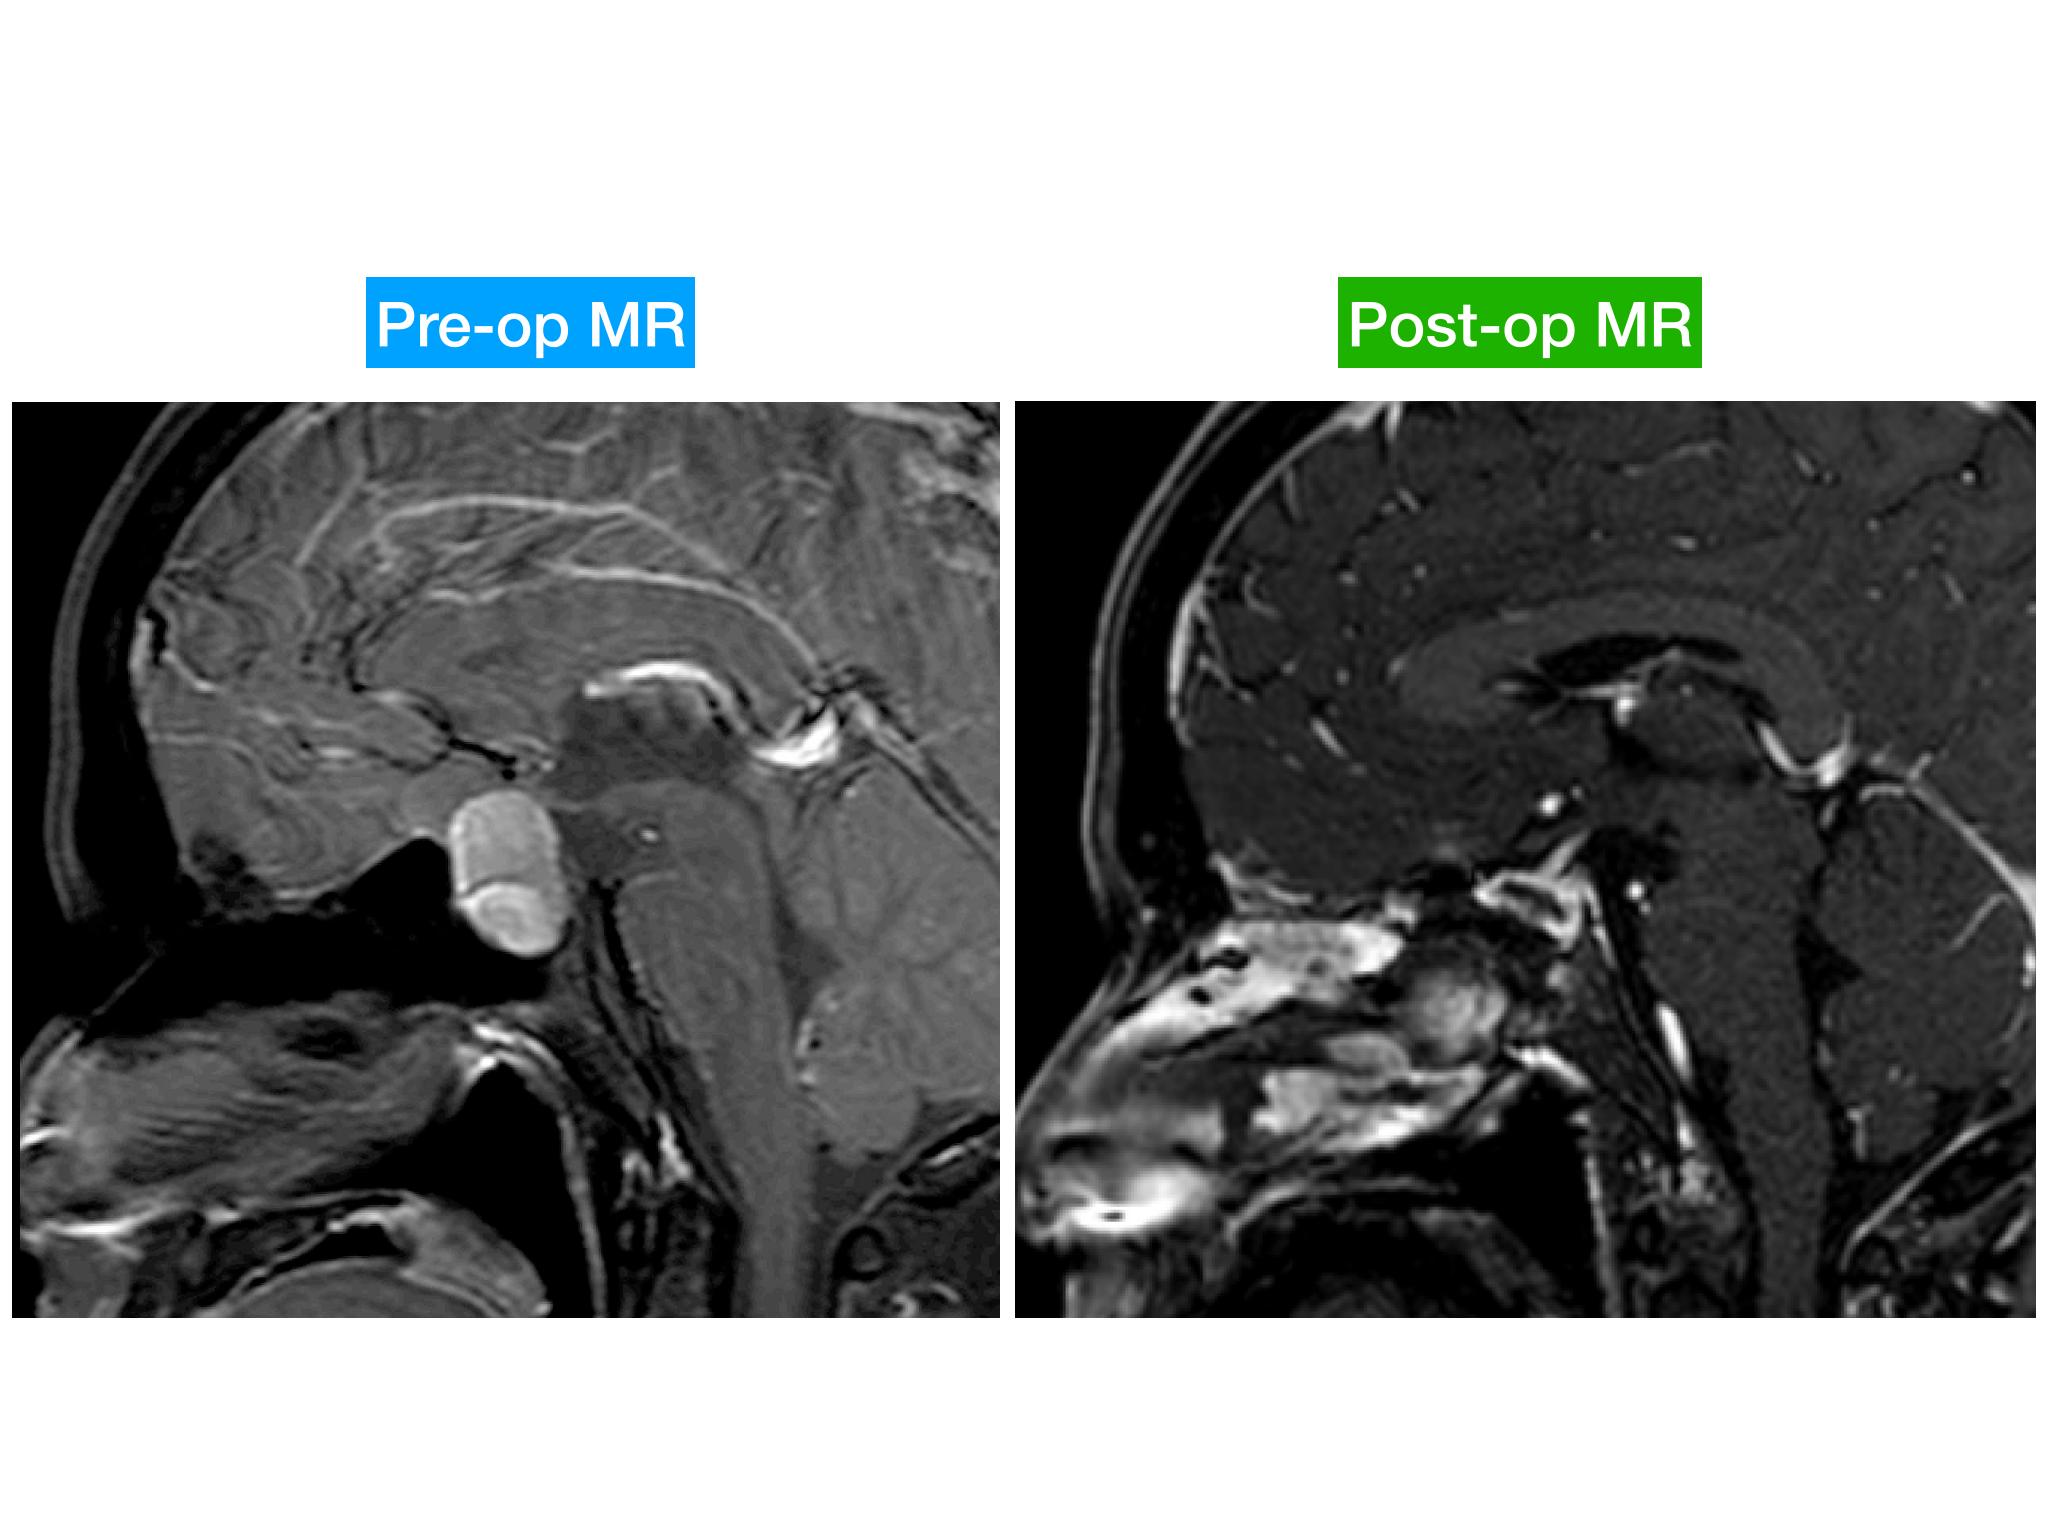

分享一例经鼻内镜泌乳素大腺瘤切除手术,患者青年男性,术前泌乳素>200ng/dl,MR提示大腺瘤合并瘤内出血,手术全切肿瘤,术后泌乳素降至正常,生化缓解,预后良好。